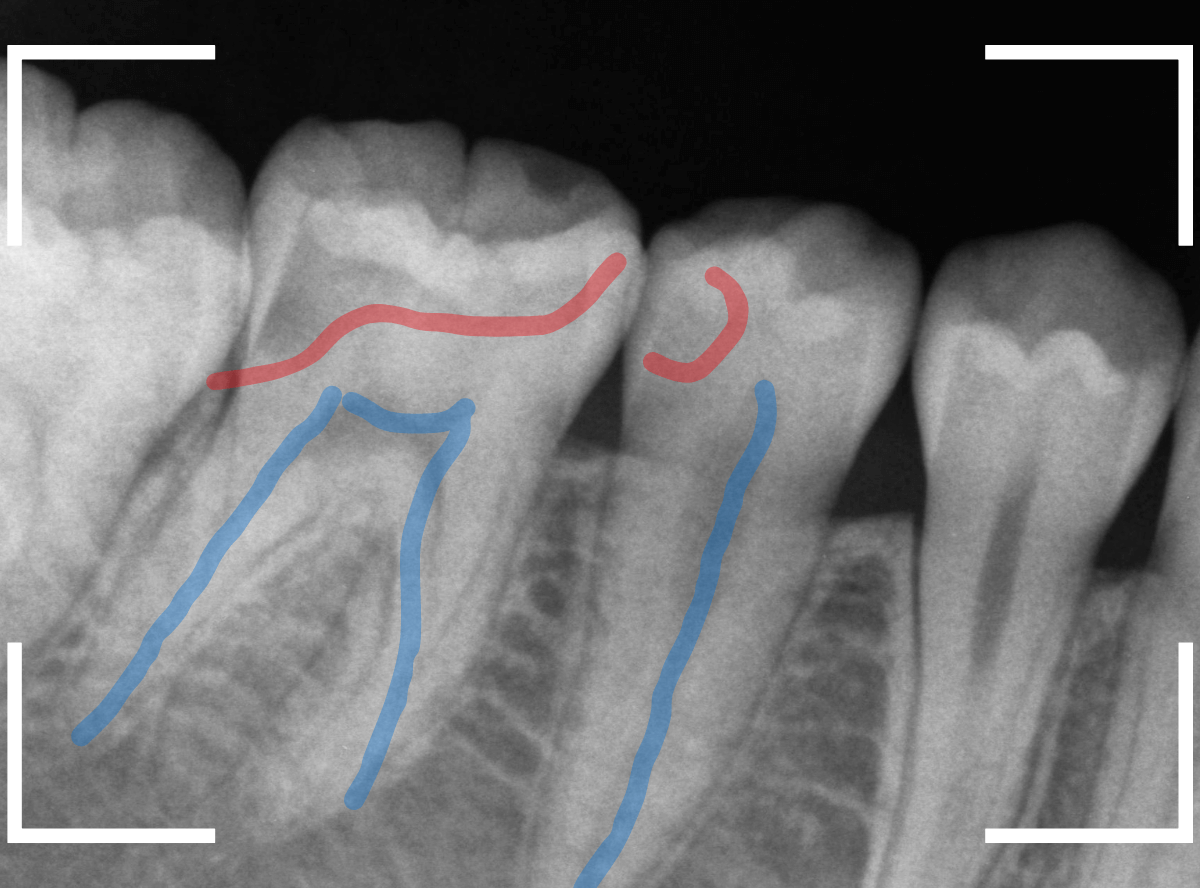

Case.1 小窩裂溝う蝕~無事にジルコニア・インレーへ

今回は、歯の溝(小窩裂溝)の下が深い虫歯になっていた方のケースです。

小窩裂溝とは、歯の表面にある小さな窪みや穴、溝のことです。

小窩裂溝は虫歯になりやすい上、歯の内部で広がっていることが多いのが特徴です。

この方は、以前にセメントで小窩裂溝を埋めて虫歯予防処置を施した形跡がありますが、それでも虫歯になってしまいました。

レントゲン写真で確認します。

青い線が神経、赤い線が虫歯の部分です。

やはり、小窩裂溝の中で大きな虫歯になっています。

奥歯から治療を開始します。

少し削ると、すぐに虫歯の部分が出てきました。

慎重に虫歯を削っていきます。

レントゲンから想像した通り、手前の歯まで達した、かなり大きな虫歯です。

赤く染まっている部分が、まだ虫歯が残っている箇所です。

歯の神経が近いので、余分に削りすぎないように、より慎重に虫歯を除去します。

全ての虫歯を除去しました。

奥歯は、レントゲン所見とおり、かなり深い虫歯でした。

神経に近い部分まで削る必要がありましたので、お薬をつめてしばらく経過観察します。

さて、しばらく経過観察後、幸い症状もありませんでしたので、最終修復に入ります。

ここで、患者さんはセラミック修復を希望されましたので、奥歯をジルコニア・インレー、手前をE-MAXインレーを製作しました。

最終setした状態です。

set後も症状なく、患者さんにも、満足していただける仕上がりになりました。

| 治療回数 | 3回 |

| 治療期間 | 1ヶ月 |

| 費用 | E-MAX・インレー (50,000円) ジルコニア・インレー (70,000円) +保険治療費用など |